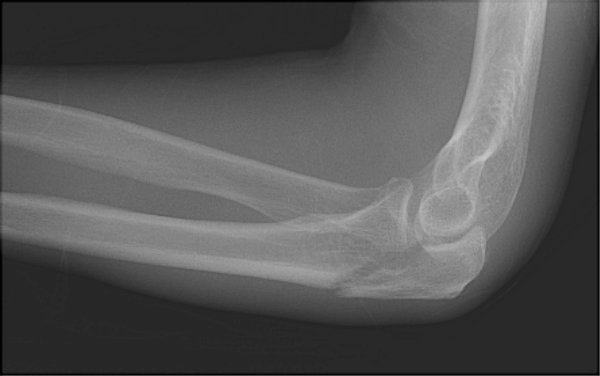

Return to Olecranon Fracture